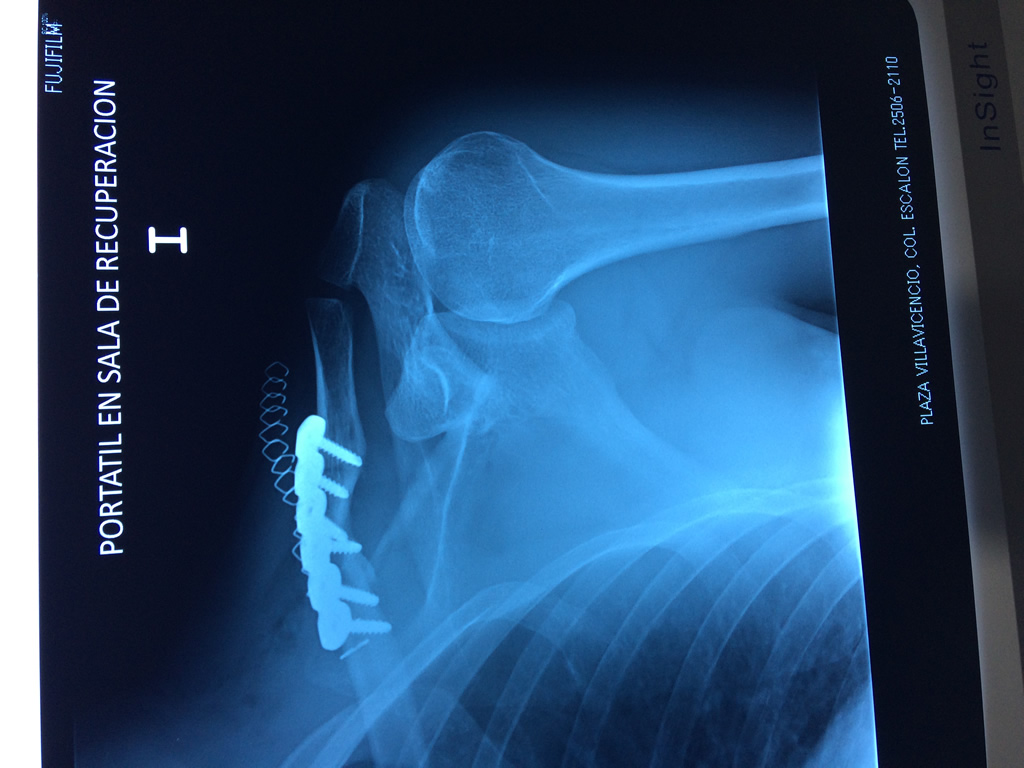

Cirugía de Fémur - Clavícula

La clavícula es un hueso largo, con forma de "S" itálica, situado en la parte anterosuperior del tórax. Junto con la escápula forman la cintura escapular. Se puede palpar por toda su longitud y se extiende del esternón al acromion de la escápula, siguiendo una dirección oblicua lateral y posterior.

Se considera el único medio de unión entre el miembro superior y el tórax. A pesar de su aspecto, similar al de un hueso largo, posee una estructura semejante a la de un hueso plano, ya que carece de epífisis y de diáfisis, lo que la harían entrar dentro de la clasificación de hueso largo. Carece de un canal medular propiamente dicho.